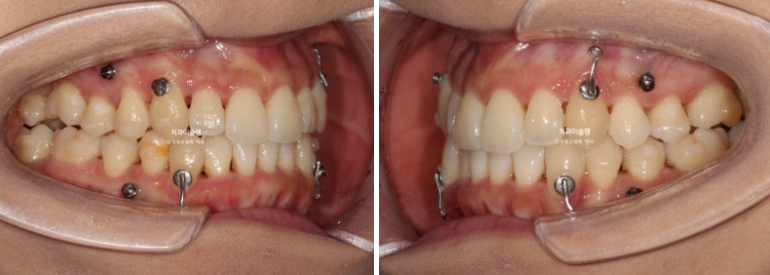

파란화살표는 가위교합입니다.

인비절라인 치료를 선택하셨고 아래 매복사랑니 1개를 빼고 위에는 사랑니 대신 양쪽 제 2대구치를 빼고 치료에 들어갑니다.

어금니 후방이동을 위한 교정용 나사도 심고

사랑니는 초반부터 장치가 잘 맞지 않아 잘라낸 후 치아에 걸어놓는 고무로 회전을 도모합니다.

첫세트 장치는 70개가 나왔습니다만 재제작은 50단계에 들어갔습니다